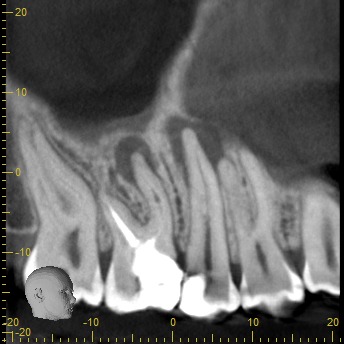

En nuestra clínica en Bogotá contamos con equipos de tomografía CBCT de última generación, que garantizan la más alta calidad en diagnóstico dental y permiten a tu odontólogo planificar cada detalle de tu tratamiento con máxima precisión.

• Rápido – Cómodo – Eficaz: Las imágenes obtenidas con nuestros equipos son altamente detalladas, mostrando los tejidos duros sin perder calidad.

Podemos analizar la posición y orientación de estructuras críticas como los nervios, las raíces dentales, los senos paranasales y la nariz, lo que ayuda a lograr un diagnóstico lo más preciso posible. Con nuestra tecnología de imagen avanzada, tu odontólogo podrá monitorear la estabilidad a largo plazo de tus restauraciones dentales, de esta forma se podrá obtener el resultado estético que deseas con tu tratamiento.